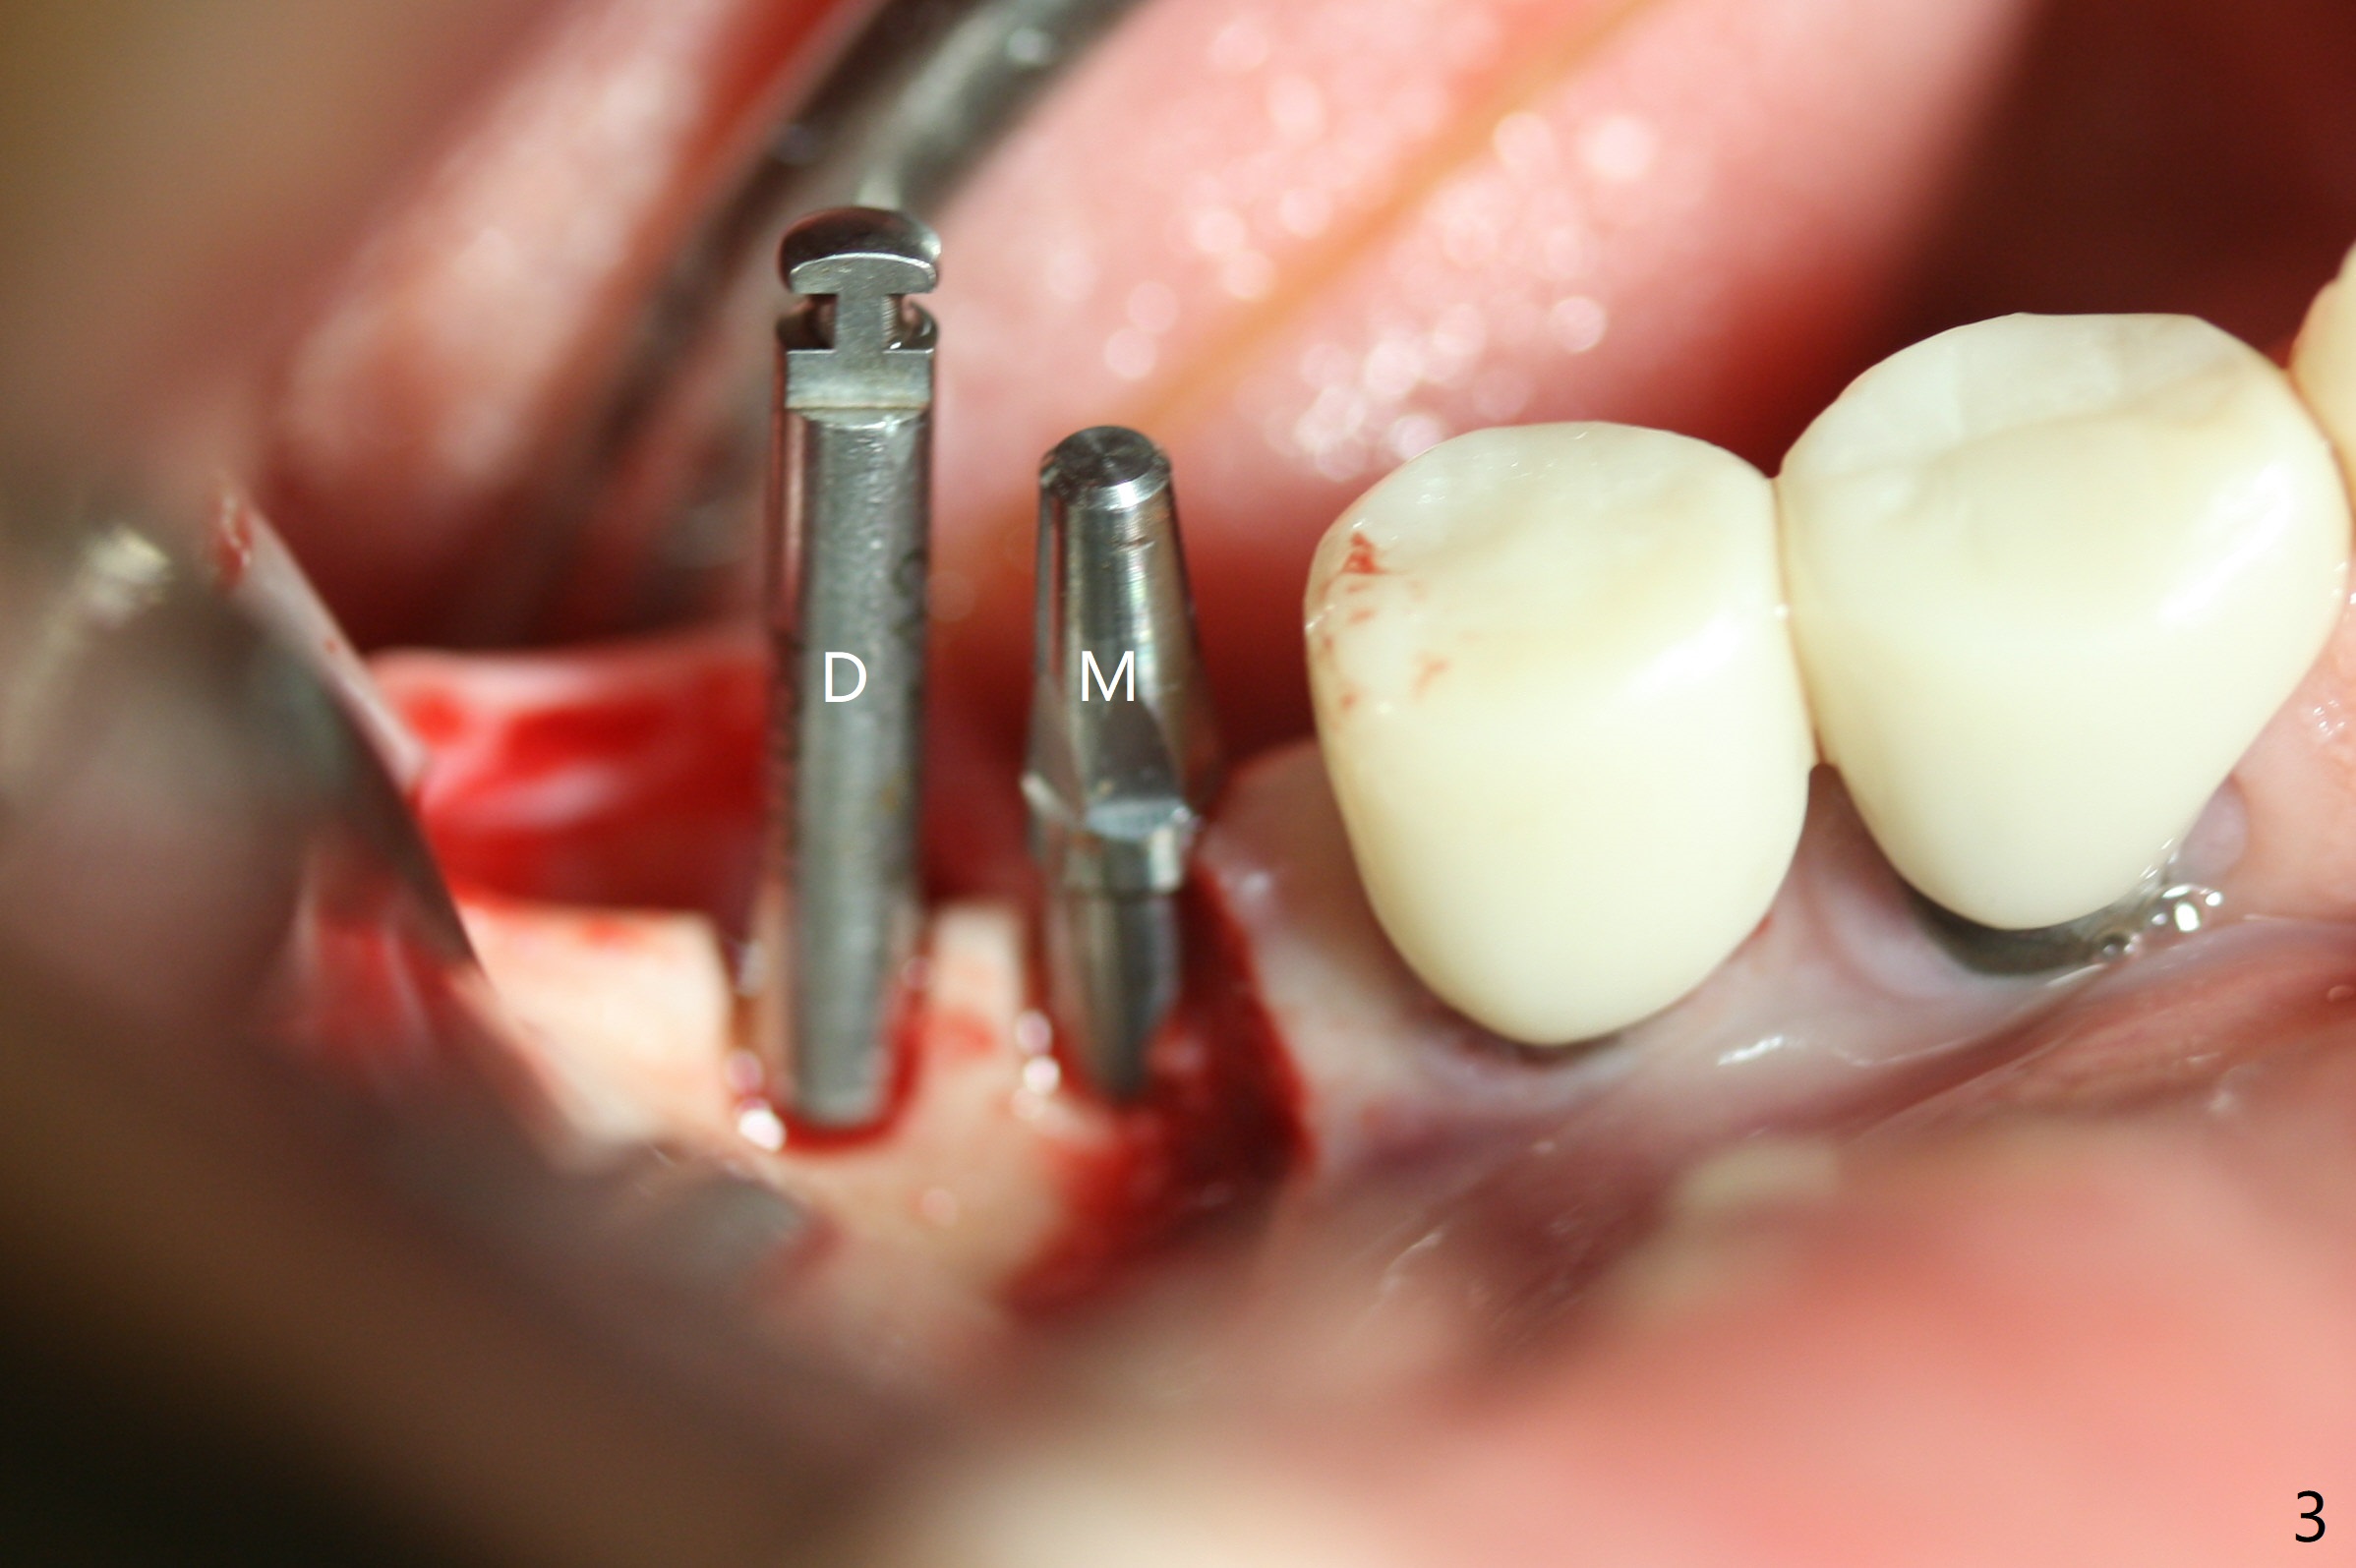

Two of 2.5 mm 1-Piece Implants M

The edentulous ridge at #30 is narrow (Fig.1). After ridge reduction, osteotomy is initiated with 1.2 mm drill for 10 mm; the mesial osteotomy is to be changed (Fig.2 red line). Using a 1.2 mm drill placed in the distal osteotomy (Fig.3 D), the mesial osteotomy changes in trajectory with subsequent placement of a 2.5x10(4) mm 1-piece implant. Since the mesial implant is high in occlusion, the cuff of the distal implant is changed to be 2 mm (Fig.4 (shorter black line)). Panoramic X-ray is taken to show no violation of the Inferior Alveolar Canal (Fig.5 red dashed line). These two 1-piece implants are slightly lingually placed (Fig.6). The crestal bone around the implants resorbs without thread exposure 5 months postop (Fig.7). Impression is taken for a splinted crown (Fig.8-12). There is no metal show around the 2.5 mm 1-piece implants 6 months postop (advantage) vs. that at #28 and 29 (Fig.13). Bitewing is taken post cementation to determine whether residual cement is present (Fig.14). There is periodic swelling and pain in the lower right quadrant 2 years post cementation (Fig.15). In fact periimplantitis appears to have developed at #28 (Fig.16) with loss of the buccal bone (Fig.17,18). The buccal bone loss is less at #29 (Fig.19) and #20 (Fig.23) and no at #30 mesial and distal implants (Fig.20,21). A much smaller implant will be placed lingually at #28 immediate (Fig.24,25).